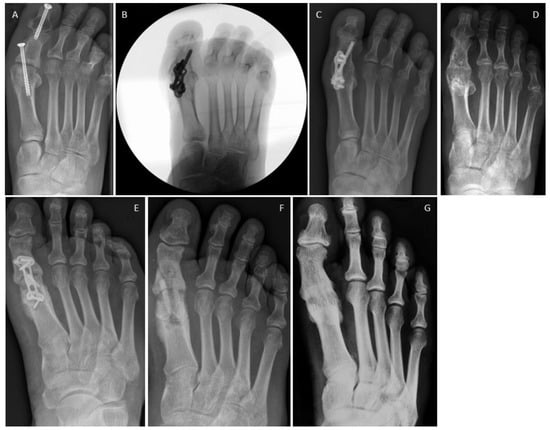

3.4. Examples for Bone Healing

3.6. Radiological Findings of Interest